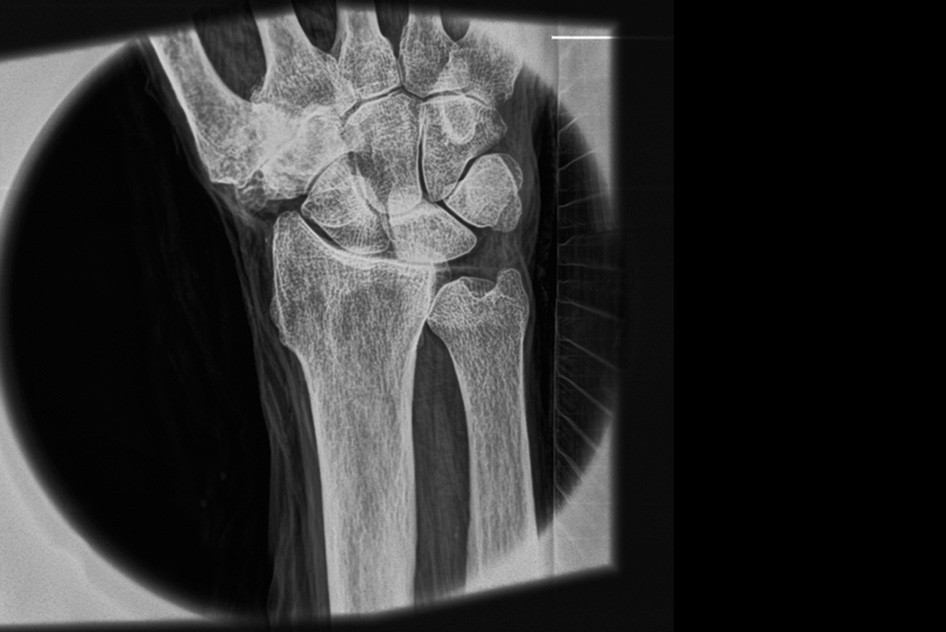

| Снимок запястья, демонстрирующий способность системы «видеть» мягкие ткани. Источник: Luis Velásquez-García et al |

Рентгеновские аппараты не дают возможности получать снимки мягких тканей без контрастных агентов наподобие бария, и разрешение таких снимков невелико. Разработка специалистов Массачусетского технологического института и Массачусетской больницы общего профиля обещает кардинальные перемены: гораздо более детальные снимки, в том числе мягких тканей, без контрастных агентов. К тому же аппарат из МТИ компактнее традиционных и выдает меньшую дозу облучения.